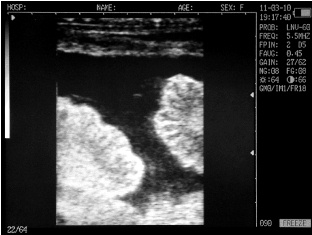

Ultrasound images of cows reproductive system, generated by a scanner Sonovet with rectal linear transducer.

Ovary cows in mid-cycle

Corpus luteum in the ovary of the cow